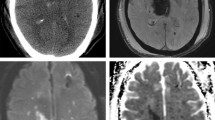

Xe-CT

In Xe-CT, inhaled stable xenon gas is used as a contrast agent [30]. Xenon is an inert, radiopaque gas that diffuses freely over the blood-brain barrier. A gas mixture with 28% xenon was delivered to the patient via the ventilator. After two unenhanced baseline scans, repeated scans of four 1-cm-thick slices with 1-cm gap were done during the wash-in phase of xenon. Quantitative CBF values were calculated from the dynamic changes in attenuation via a modified Kety-Schmidt equation. A system with a mobile CT scanner was used, which enables CBF measurement to be done bedside at the NICU. This was considered an advantage since severely ill patients may be impossible to transfer from the NICU for CBF measurements. The measured CBF values probably also better reflect the values during neurointensive care, rather than values measured at the radiology department, where ventilation and sedation parameters are likely to be different.

CPPΔ was moderately negatively correlated with CBF% <10, CBF% <20 and mean global CBF with borderline significance. Mean CPP was not correlated with any of the CBF parameters (Table 3). Patients with actual CPP below CPPopt had significantly higher amounts of CBF% <10 (median 5% vs. 0%, p = 0.008, Mann-Whitney U-test, Fig 1).

This is, to our knowledge, the first study to investigate the relation between CPPopt and CBF in SAH patients. CPPopt could be calculated in adjunct to at least one Xe-CT scan in 78% of the patients and in 60% of all Xe-CT scans performed, using data from a 4-h time window. The fact that CPPopt could not be calculated in all patients is of course a limitation, but the numbers are reasonably high to be of use clinically. ΔCPP was negatively correlated with CBF% <10 and CBF% <20, meaning that patients with actual CPP < calculated CPPopt had higher numbers of low-flow regions (Table 3, Fig 1). The effect was not attributed to the CPP level per se, as CPP itself was not correlated with any of the CBF parameters in any of the time windows (Tables 2 and 3). This suggests that CPP in SAH patients should be individualized according to the status of autoregulation and that low CPP in relation to the calculated optimum should be avoided. The findings were consistent in both the early (day 0–3) and late (day 4–14) time windows, but were more clear when data from all monitoring times were used, possibly because of the larger sample size. In the two time windows with smaller sample size, actual CPP above CPPopt was associated with a lower number of regions with CBF <10 ml/100 g/min. This is clinically important since CBF 10 ml/100 g/min is very close to ischemic levels [19, 30].